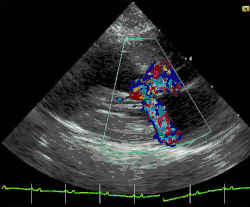

.jpg)

A diagnosis of hypertrophic cardiomyopathy is based upon several features of the disease process. While there is use of echocardiography, cardiac catheterization, or cardiac MRI in the diagnosis of the disease, other important considerations include ECG, genetic testing (although not primarily used for diagnosis),[33] and any family history of HCM or unexplained sudden death in otherwise healthy individuals. In about 60 to 70% of the cases, cardiac MRI shows thickening of more than 15 mm of the lower part of the ventricular septum. T1-weighted imaging may identify scarring of cardiac tissues while T2-weighted imaging may identify edema and inflammation of cardiac tissue which is associated with acute clinical signs of chest pain and fainting episodes.[34]

ECG is the most sensitive diagnostic test.[17] The combination of left ventricular hypertrophy, and right atrial enlargement on ECG strongly suggests HCM.[17]

Depending on whether the distortion of normal heart anatomy causes an obstruction of the outflow of blood from the left ventricle of the heart, HCM can be classified as obstructive or non-obstructive.[35] The obstructive variant of HCM is hypertrophic obstructive cardiomyopathy (HOCM), also historically known as idiopathic hypertrophic subaortic stenosis (IHSS) or asymmetric septal hypertrophy (ASH).[36] The diagnosis of left ventricular outflow tract obstruction is usually made by echocardiographic assessment and is defined as a peak left ventricular outflow tract gradient of ≥ 30 mmHg.[35]

HCM can be detected with an echocardiogram (ECHO) with 80%+ accuracy,[44] which can be preceded by screening with an electrocardiogram (ECG) to test for heart abnormalities. Cardiac magnetic resonance imaging (CMR), considered the gold standard for determining the physical properties of the left ventricular wall, can serve as an alternative screening tool when an echocardiogram provides inconclusive results.[45] For example, the identification of segmental lateral ventricular hypertrophy cannot be accomplished with echocardiography alone. Also, left ventricular hypertrophy may be absent in children under thirteen years of age. This undermines the results of pre-adolescents' echocardiograms.[15] Researchers, however, have studied asymptomatic carriers of an HCM-causing mutation through the use of CMR and have been able to identify crypts in the interventricular septal tissue in these people. It has been proposed that the formation of these crypts is an indication of myocyte disarray and altered vessel walls that may later result in the clinical expression of HCM.[45] A possible explanation for this is that the typical gathering of family history only focuses on whether sudden death occurred or not. It fails to acknowledge the age at which relatives had had sudden cardiac death, as well as the frequency of the cardiac events. Furthermore, given the several factors necessary to be considered at risk for sudden cardiac death, while most of the factors do not have strong predictive value individually, there exists ambiguity regarding when to implement special treatment.[46]